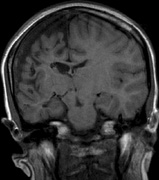

Intracranial leptomeningeal capillary vascular malformation (Figs. 21 and 22) is associated with seizures and contralateral neuromuscular weakness. Central nervous system involvement correlates highly with ipsilateral involvement of the V1 dermatome by a PWS.208,218

Fig. 22. Axial T2-weighted (a) and coronal T1-weighted (b) images of a 16-year-old boy with a port-wine lesion over the right side of his face. The right hemisphere is markedly atrophic and abnormal draining veins are seen within the right lateral ventricle (arrowheads). (c, d) The entire right hemisphere is covered by an enhancing pial angioma and the choroid plexi are enlarged. Enhancing retinal angiomas (arrows), typical of Sturge-Weber syndrome, are seen in (d).